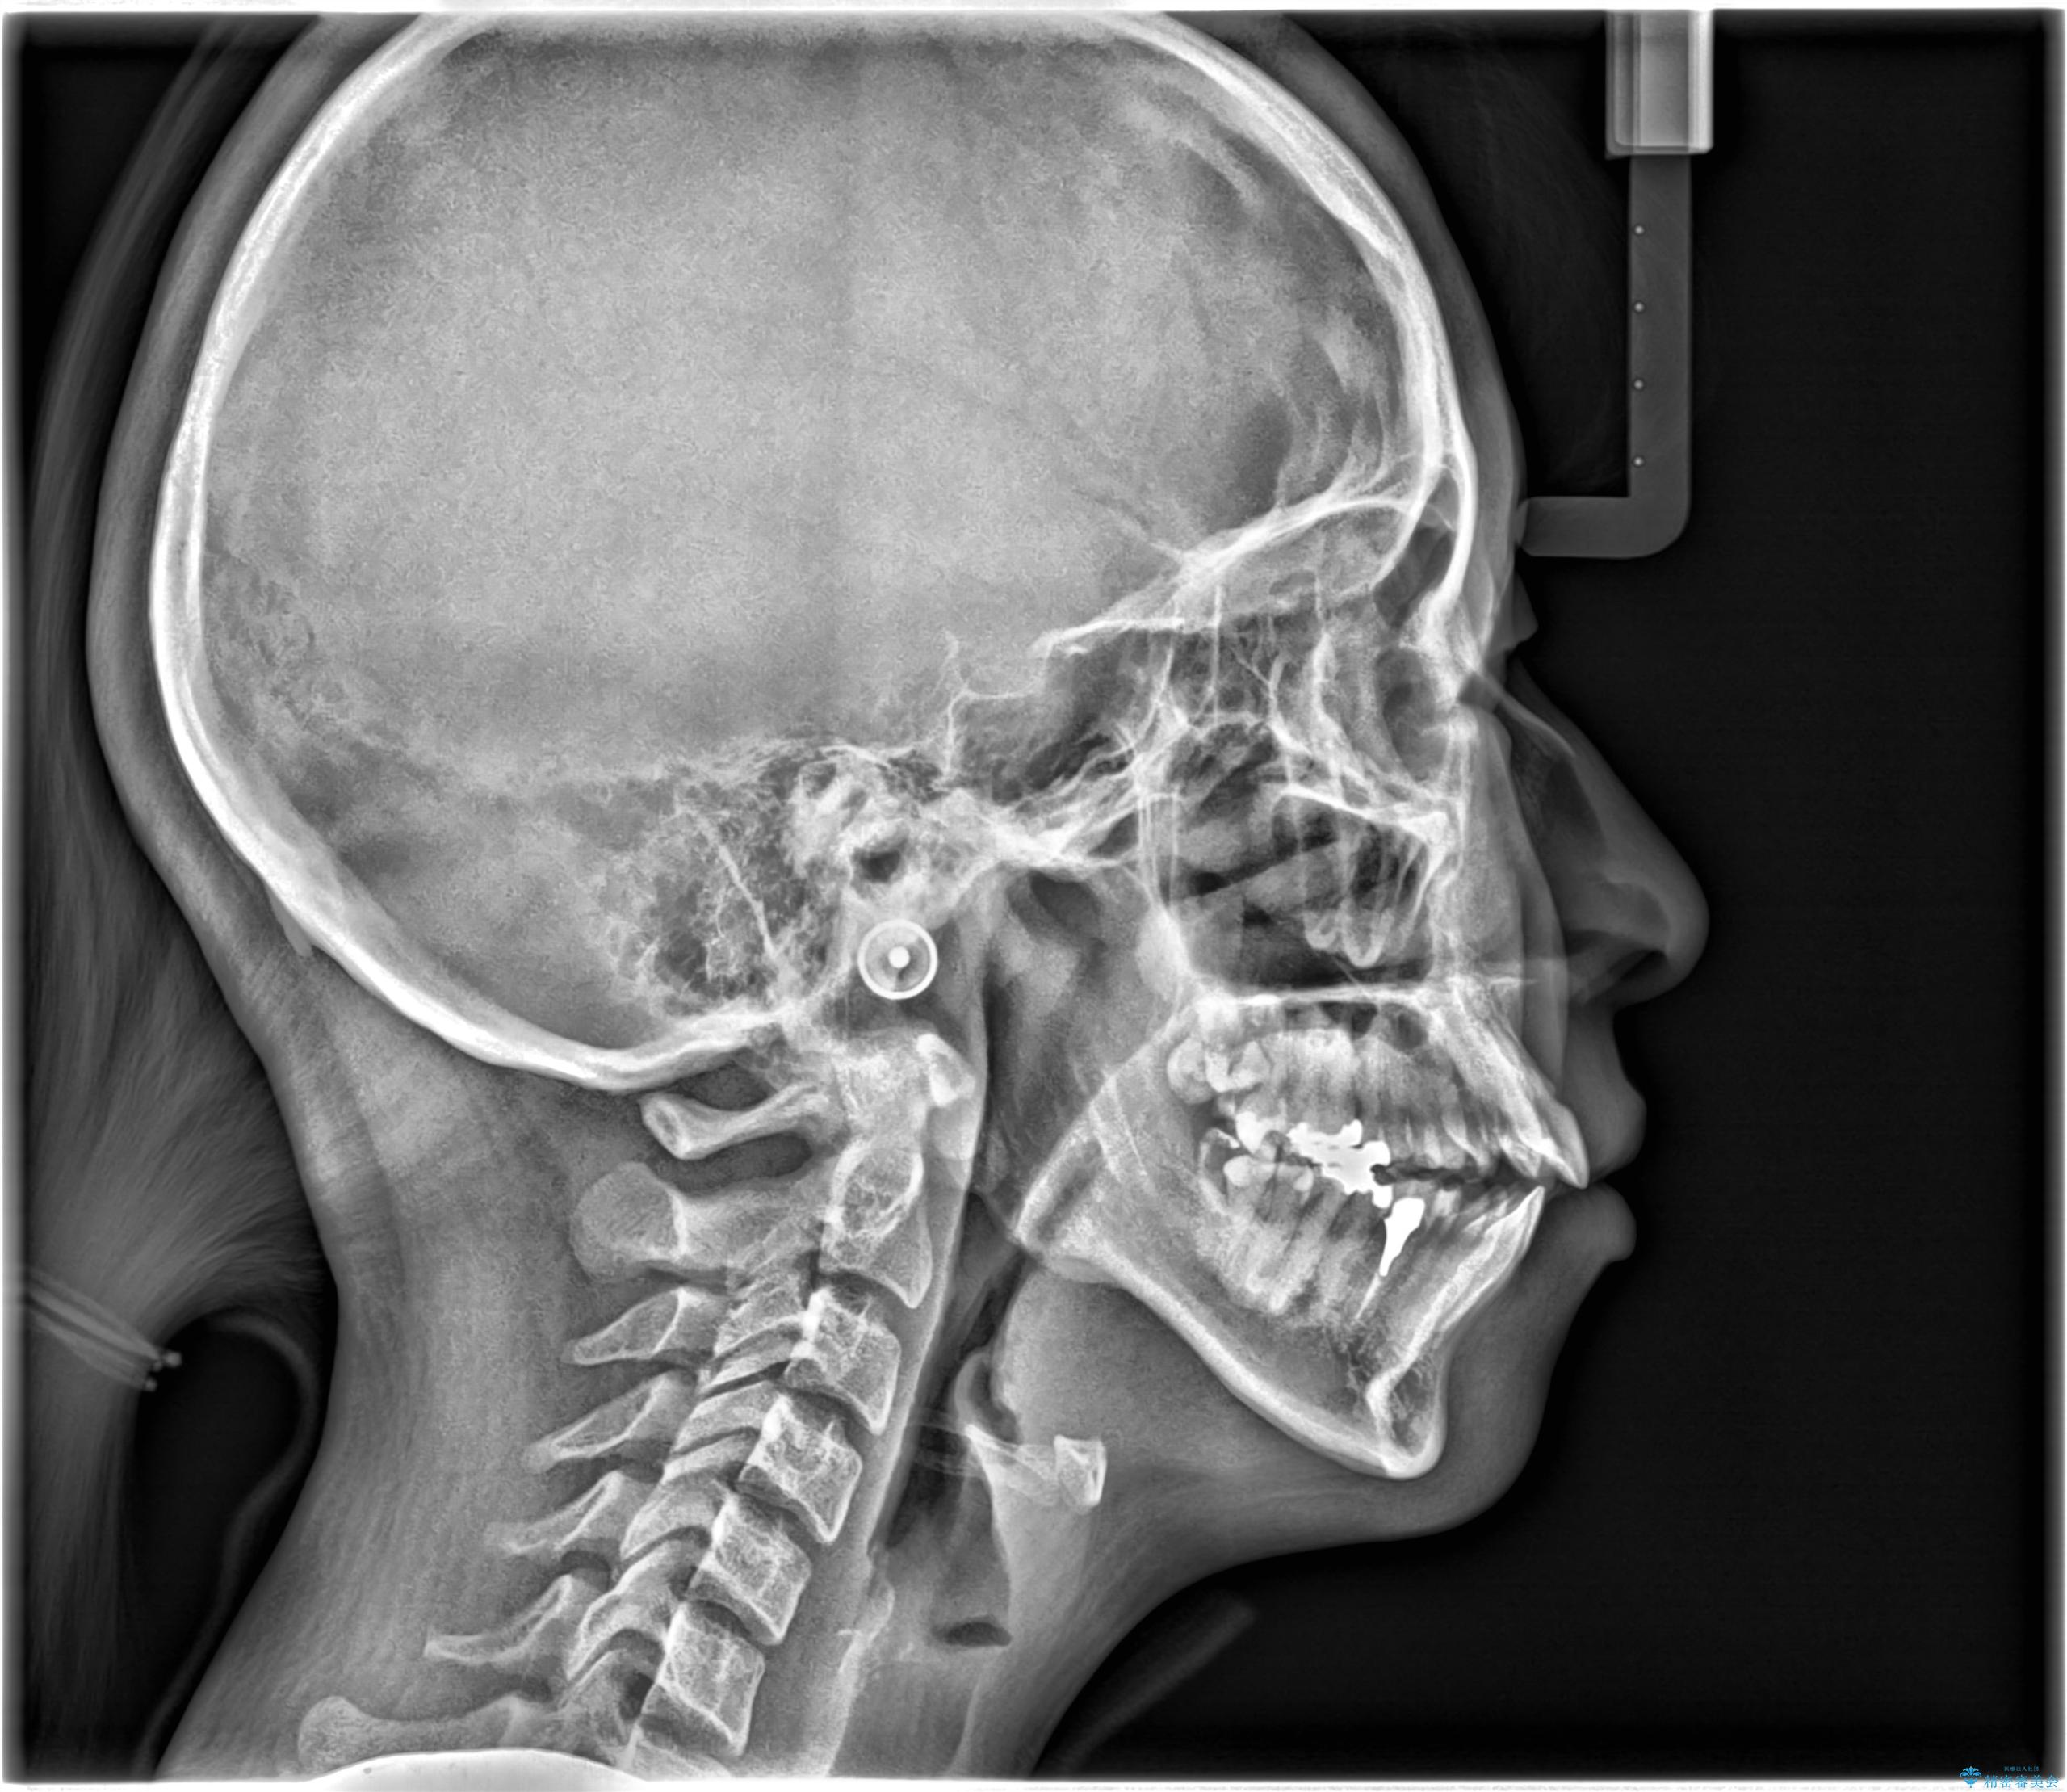

- 開咬と歯のデコボコ(叢生)、八重歯を主訴にご来院された患者様です。

矯正の精密検査の結果、上顎左右4番および下顎左右5番の計4本を抜歯し、ワイヤー矯正(クリア装置)にて治療を行いました。